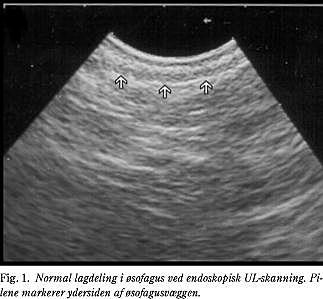

Selve undersøgelsen

EUS udføres normalt i let sedation, og ud over at patienten skal være fastende, er der ingen forberedelser. Fordelen ved undersøgelsen er, at man er tæt på de strukturer, der skal undersøges, og da der anvendes højfrekvent ultralyd, opnås der et billede med mange detaljer (Fig. 1 ). EUS er derfor velegnet til at vurdere en malign tumors lokale udbredelse (T-stadium) og involveringen af regionale lymfeknuder (N-stadium), men derimod kan man ved undersøgelsen sjældnere udtale sig om metastaser (M-stadium), da man kun undersøger et relativt begrænset udsnit af patienten. En anden ulempe ved EUS er, at den må betragtes som en invasiv undersøgelse. Frekvensen af alvorlige komplikationer efter EUS angives at være under 0,5% (2, 3); hos patienter med stenoserende øsofaguscancere er øsofagusperforation den hyppigst forekommende komplikation. Imidlertid forøges komplikationsfrekvensen, hvis der foretages EUS-FNA, idet den anføres til at være over 3% ved bioptering af forandringer i pancreas (4). Af denne årsag og pga. de relativt høje materialeudgifter ved EUS-FNA bør man kun udføre denne, såfremt svaret har betydning for den videre behandling (5).